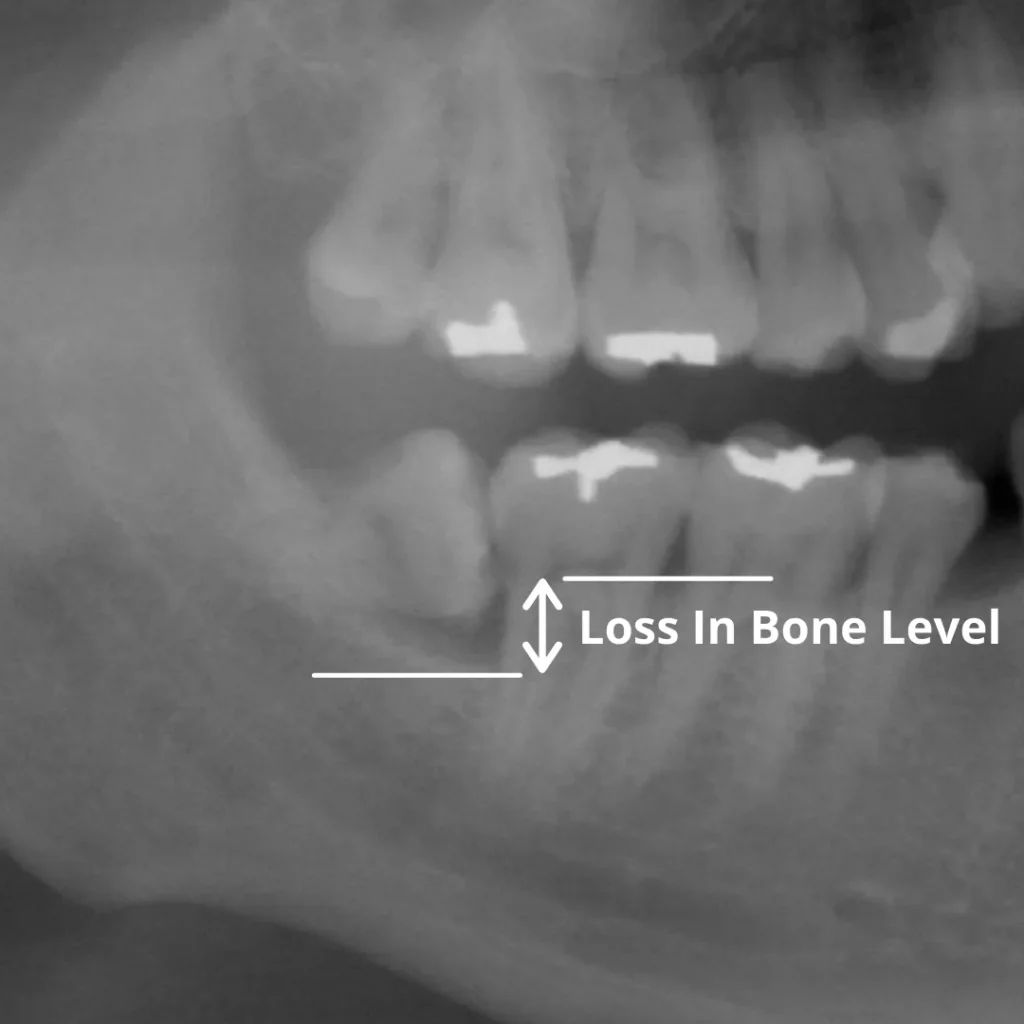

In this x-ray, we can see a partially impacted wisdom tooth that has led to periodontal disease, with heavy plaque accumulation causing significant bone loss around the tooth next to it. Bone loss, in turn, makes the otherwise healthy tooth more likely to require extraction in the future.

You can read more about periodontal disease and bone loss here.